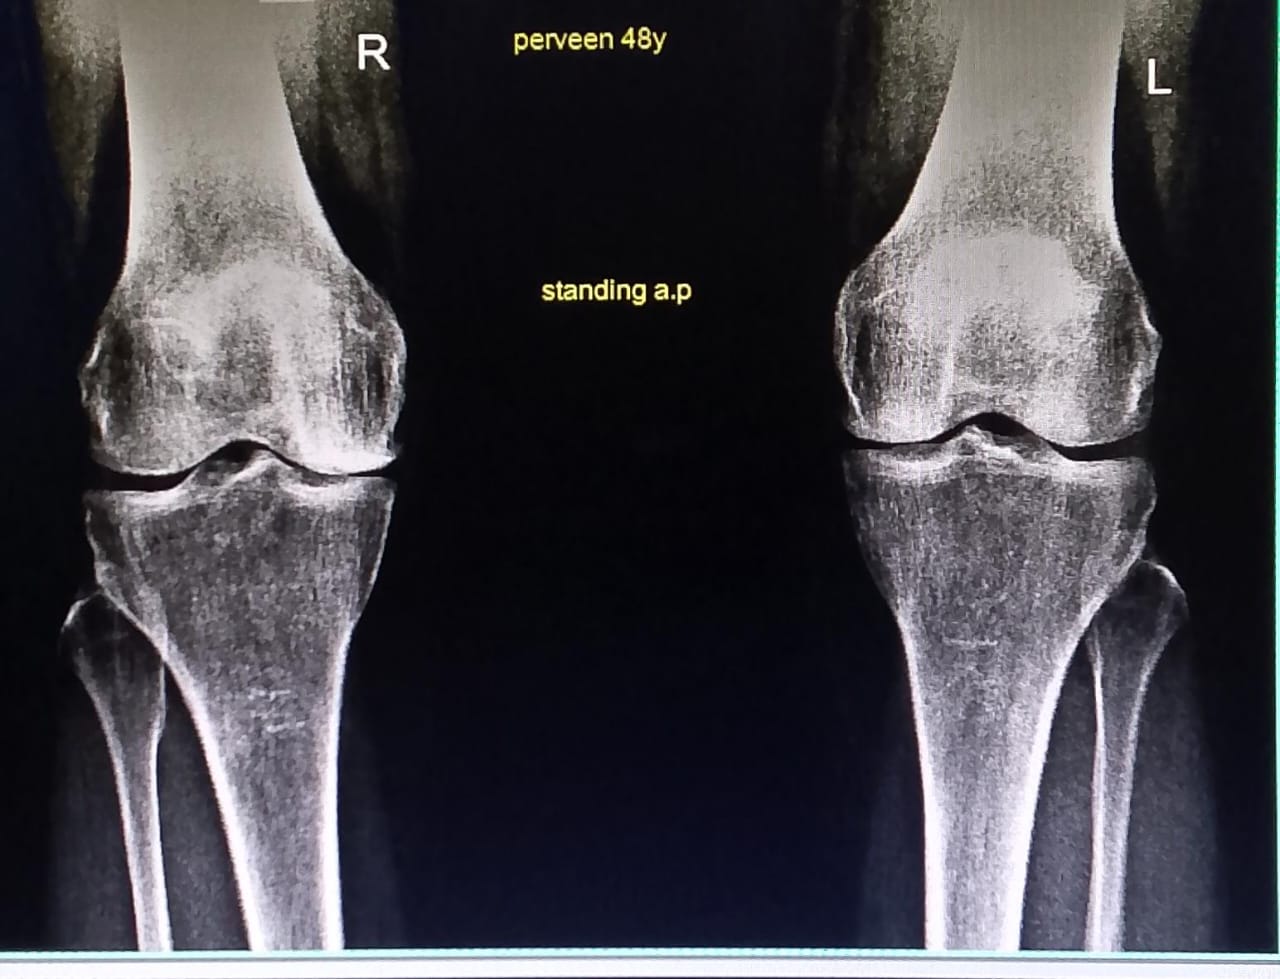

there are features of early arthritis. get examined to discuss possible options.

arthritis...if not improved by medicines then can go for intra articular injection or knee replacement

It's arthritis. You can to take some precautions and over the counter pain killers for exacerbated pain.